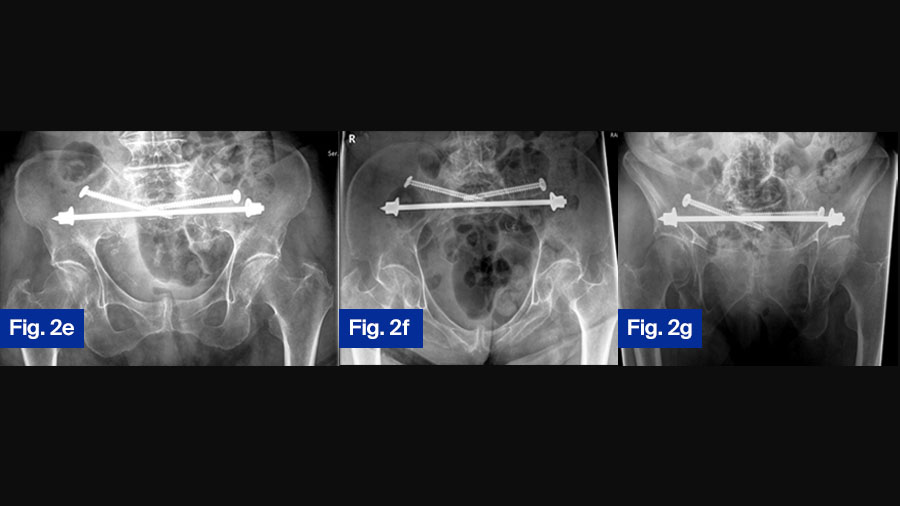

There are different minimal-invasive techniques, which can be used for stabilization of the posterior and anterior pelvic ring. Prerequisite is a thorough preoperative analysis of the specific anatomy of the pelvic ring of each patient, including the measurement of the intra-osseous corridors, through which implants can be inserted. The techniques and implants for the posterior pelvic ring are: ilio-sacral screw osteosynthesis, cement augmentation of ilio-sacral screws, trans-iliac trans-sacral screws, trans-sacral bars (Figure 2a-g), trans-iliac internal fixator, and lumbo-pelvic fixation [6]. Techniques and instruments for the anterior pelvic ring are: retrograde transpubic screw, pelvic bridge, internal fixator (INFIX). Multiple biomechanical studies display the varying stiffness and load-bearing stability of each system.

Case Study 2: 92-year-old female with bilateral sacral fracture (FFP Type IVb)

Figure 2. 92-year-old female patient presenting 1 week after fall from standing height with immobilizing pain at lower lumbar spine. (a) Axial CT demonstrating slight displacement of bilateral sacral fracture; (b) sagittal CT with displaced transversal fracture at S1/S2 level. The fracture was classified as FFP type IVb. (c) Lateral fluoroscopic image orientated in direction of the patient (bottom anterior, left cranial) showing overlapping of ilio-cortical densities and ischial notch.

The drill guide is placed centrally in S1 corridor caudal to the ilio-cortical densities. (d) Oblique obturator view to assess the abutment of the washer on the iliac cortex.

Postoperative control at discharge, patient is mobile with a walker ( (e) anterior–posterior, (f) inlet, and (g) outlet view ).